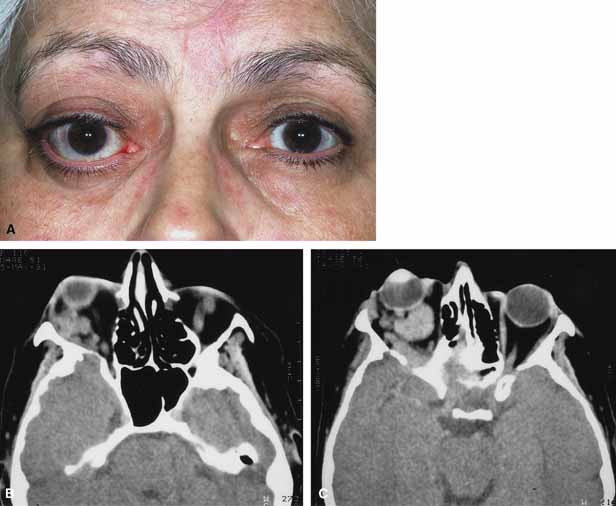

| Thyroid-related eye disease (Grave's disease) has